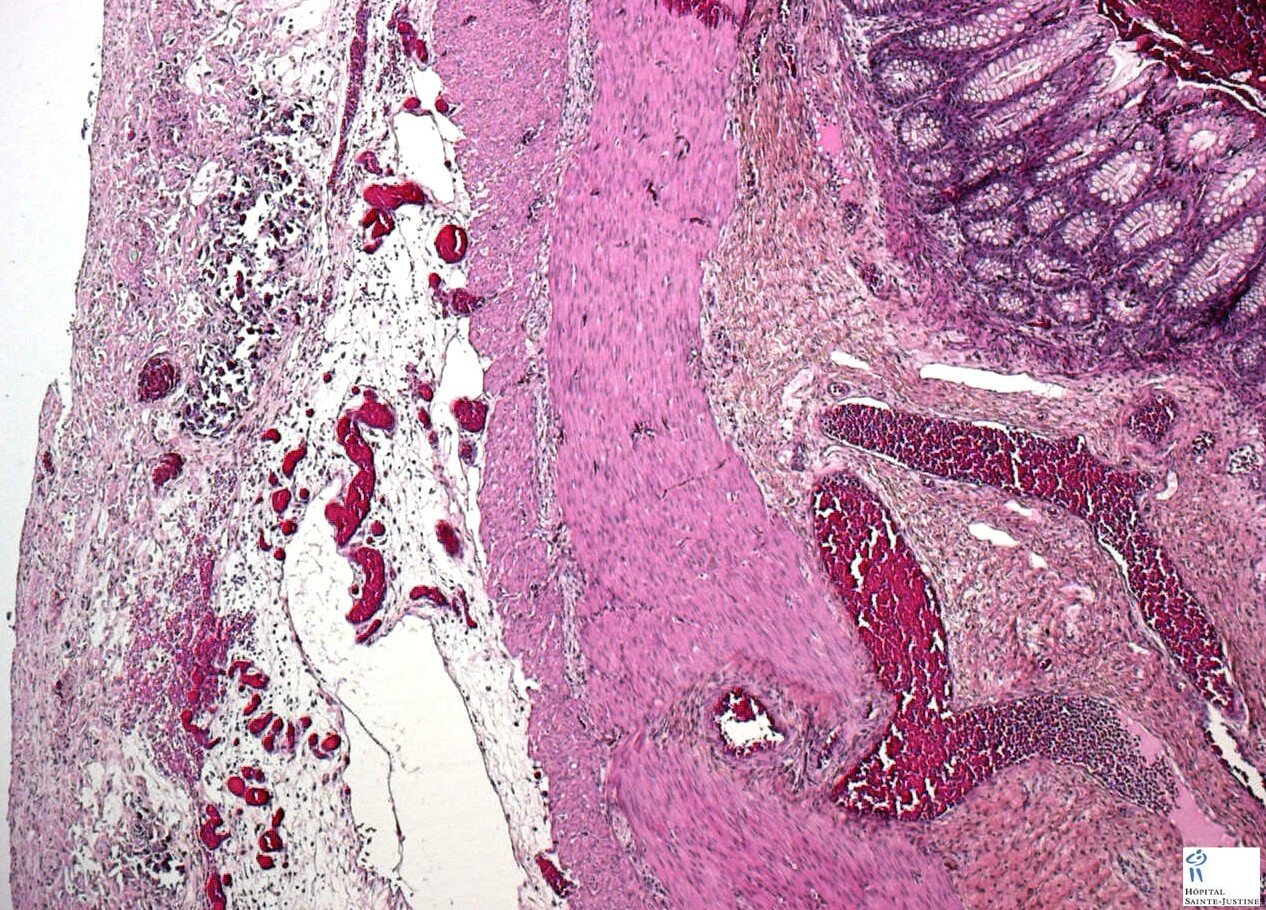

Meconial peritonitis in fetal cystic fibrosis